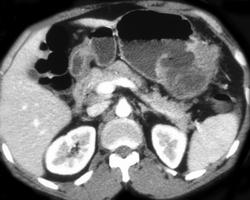

Perforated Gastric Ulcer (antrum) With Contrast Extravasation